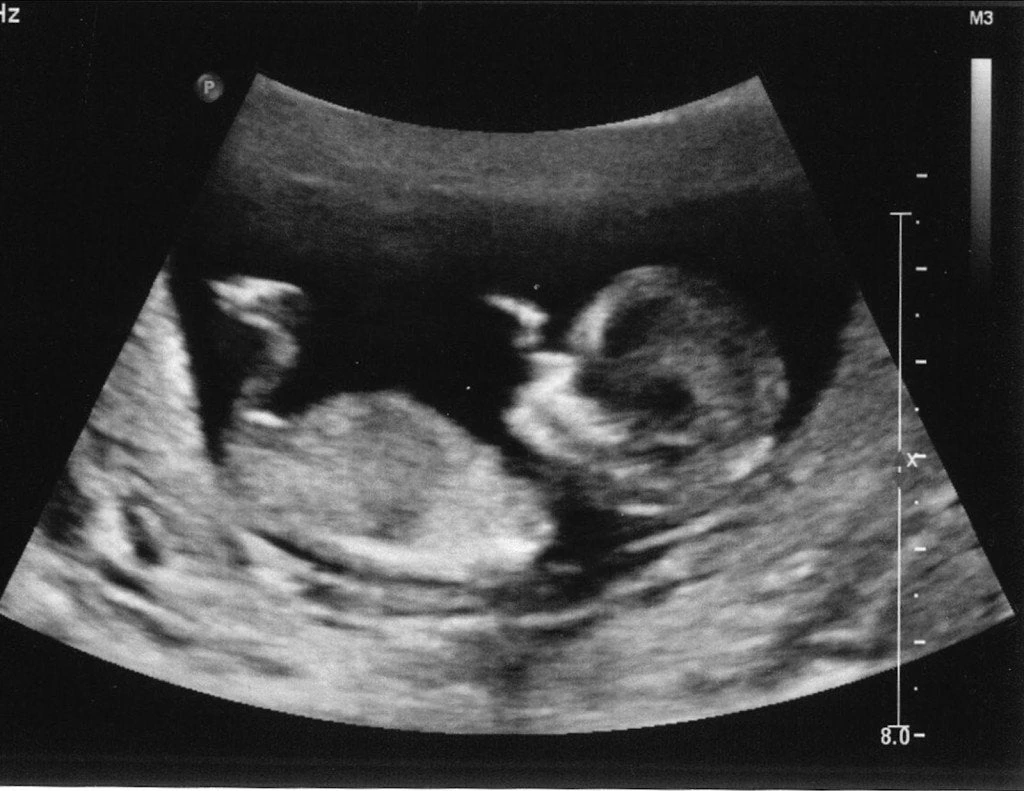

Ρόδος: Ο υπέρηχος έδειξε αυτό που φοβόταν η έγκυος μητέρα – Συγκλονίζει η τραγική ιστορία του ζευγαριού

Η έγκυος γυναίκα είχε μπει στο μήνα της και το ζευγάρι είχε ετοιμάσει τα πάντα. Τα όσα ακολούθησαν προκαλούν θλίψη και συγκίνηση… Το τραγικό της παιχνίδι έπαιξε η μοίρα σε δύο πολύ καλο...